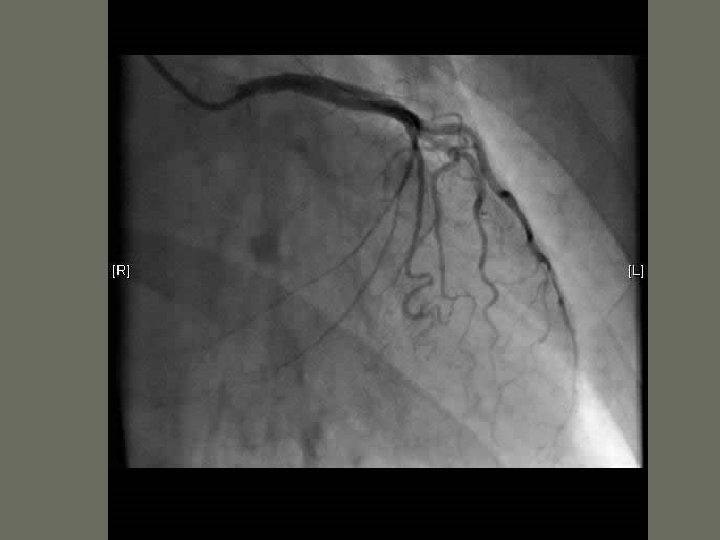

Cardiac Catheterization • one of the most common angiographic procedures performed in the US • may be performed as a cardiac ________ or angiocardiography • includes ________measurements • performed for a wide variety of problems dealing with the heart • Blood Supply to the Heart • Pulmonary Circulation

Cardiac Catheterization • Indications 1. Any condition that compromises blood _______ and ______ to the heart – chest pain – angina 2. major complication after acute ____(shock, CHF, valvular dysfunction • Contraindications 1. only absolute contraindication is the refusal of a mentally ______ patient to consent to the procedure

Cardiac Catheterization • Angiocardiography 1. radiographic evaluation of the _______ of the heart and various valves 2. hemodynamic monitoring is the evaluation and recording of the function of the heart 3. include oxygen saturation, pressure tracings, and cardiac _______